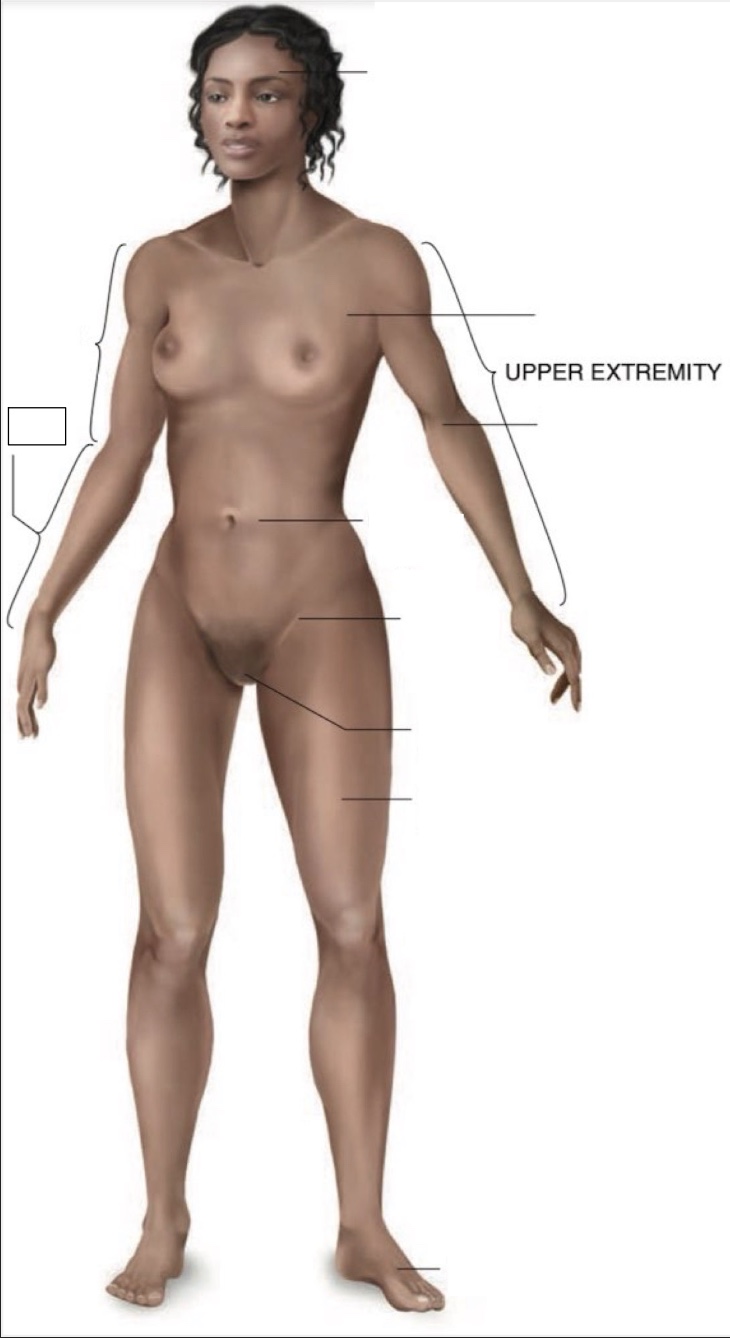

Cranial region

thoracic region

umbilical region

inguinal region

genital region

femoral region

dorsum of foot

arm

forearm

cubital region

Torso

Inferior

Midline